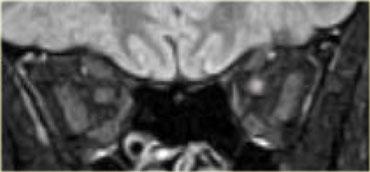

Bên trái là hình ảnh của một bệnh nhân khác với tổn thương ngoài nhãn cầu trong nón cơ.

Hãy quan sát hình ảnh, mô tả và đưa ra chẩn đoán phân biệt (tạm thời bỏ qua tiêu đề của đoạn này là u màng não).Các thần kinh thị giác bình thường, nhưng có hình ảnh ngấm thuốc dạng khối bất thường của bao thần kinh thị giác bên trái.

Do đó đây có thể là một u tân sinh, và trong số các u tân sinh, u màng não là u bao thần kinh thị giác phổ biến nhất.

U màng não biểu hiện rối loạn thị giác sớm trong quá trình bệnh do bệnh lý thần kinh thiếu máu cục bộ gây ra bởi tắc nghẽn tĩnh mạch.

Về mặt lâm sàng, biểu hiện này là đĩa thị nhợt nhạt.Ngấm thuốc bất thường của bao thần kinh thị giác